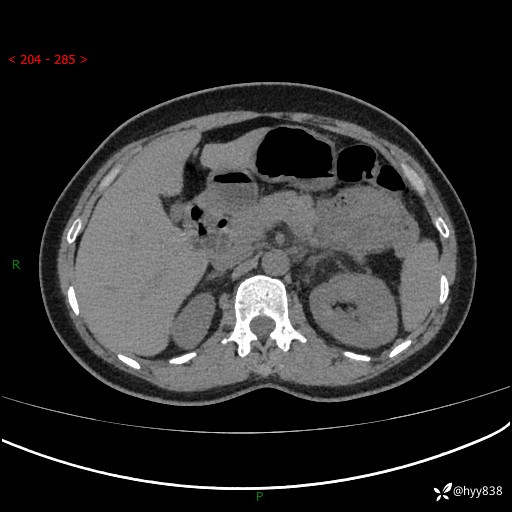

现病史:患者1天前无明显诱因下出现左上腹部及腰背部胀痛不适,阵发性加剧,伴肛门停止排气;无发热,无恶心呕吐,无畏寒发热,无心慌气短等不适,于当地市第二人民医院就诊,行腹部ct检查提示左上腹区肠系膜血管从剧聚集,分布紊乱伴肠管局限性稍扩张积液,不完全性肠梗阻;考虑子宫颈纳氏囊肿,双侧附件区囊状灶;予以抗炎及对症支持等治疗后未见明显缓解,现患者为求进一步治疗来我院急诊就诊,遂以“肠梗阻”收住入院。 病来,神志清,精神可,饮食睡眠不佳,经灌肠后排便2次,小便正常,体力体重无明显变化。

上腹部CT平扫